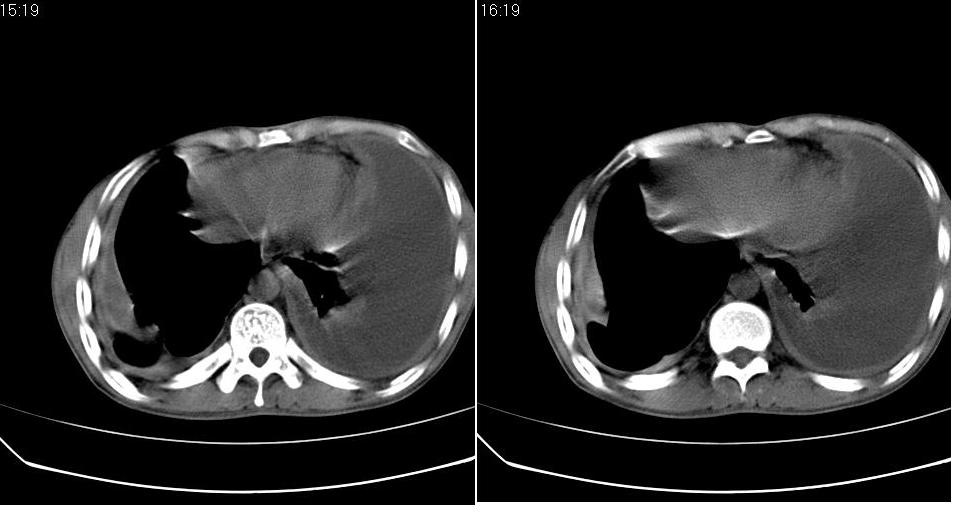

以下是引用苯小孩在2007-6-27 15:09:00的发言:[br]考虑:1、右肺继发性肺结核.2、双侧包裹性积液<胸腔及叶间>3、双侧局部胸膜增厚.[br]建议胸水化验检查.

以下是引用yanghaochen88在2007-6-27 15:08:00的发言:[br]双肺上野散在粟粒状影、包裹性积液、胸膜增厚粘连、叶间积液---tb,至于分型还得结合病史体征细究妥当些。